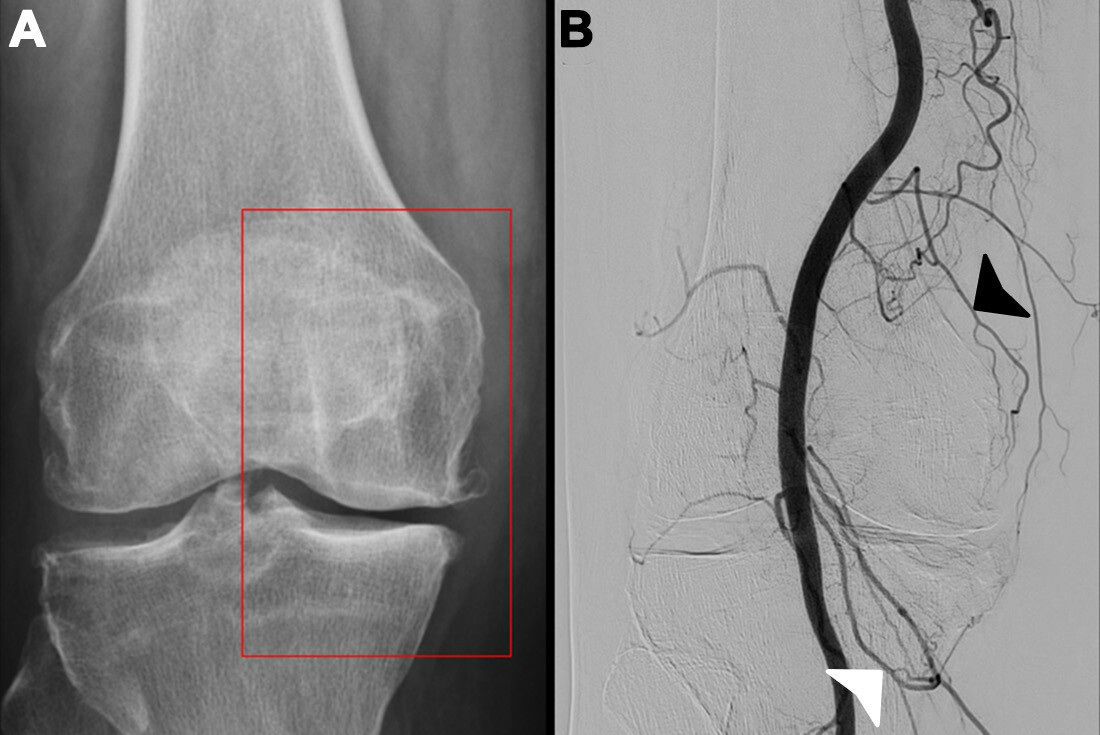

The radiologists used digital subtraction angiography (DSA), in correlation with the patients' pain points, to visualize blood vessels during the procedure, according to details at RSNA.

Peri-interventional digital subtraction angiography (DSA) of the descending genicular artery (DSA), a diagnostic procedure to view the inner surface of blood vessels, (green arrow) in a patient with symptomatic knee osteoarthritis of the right leg. On the left, the pre-interventional image with a clearly visible hyperemic blush (red box). On the right, the post-interventional DSA after embolization with Imepenem-Cilastatin. A completely eliminated blush is observed while preserving skin collaterals (orange arrows). Image courtesy of the RSNA.